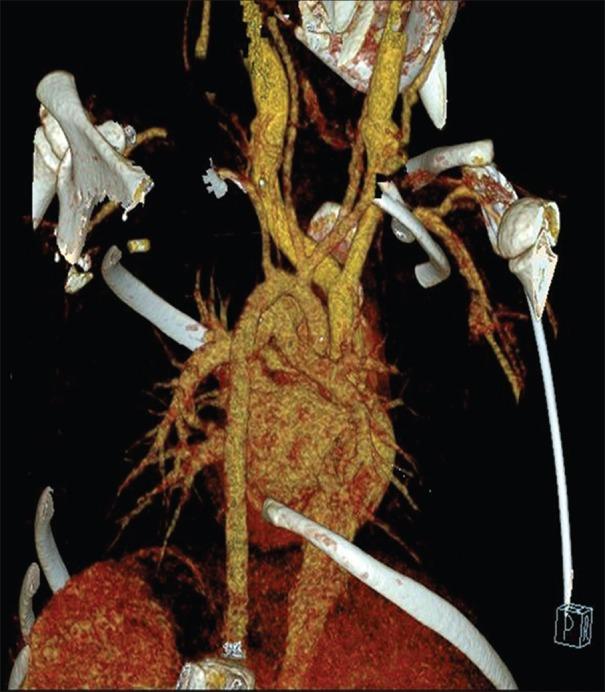

威廉姆斯-贝伦综合征是一种多系统遗传性疾病,由7号染色体长臂11.23区域的半合子缺失引起,该区域包含约28个基因,包括弹性蛋白基因ELN。心血管异常很常见,与弹性蛋白不足有关。这些异常包括70%的病例出现主动脉瓣上狭窄(SVAS)、肺动脉瓣狭窄和肾动脉狭窄。主动脉瓣上狭窄的确定性治疗包括对动脉病变进行手术矫正。SVAS手术矫正后的结果取决于动脉病变的程度和其他相关病变的存在情况。我们报告一例患有威廉姆斯-贝伦综合征并伴有SVAS的4岁男孩病例。在手术干预前,对该患者进行了计算机断层血管造影评估,以确定主动脉病变的程度。